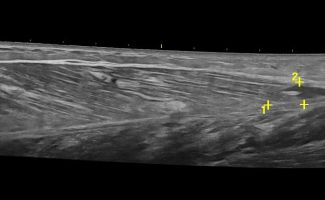

- Κατηγοριοποίηση (Grading) Θλάσεων Μυών: Το Υπερηχογράφημα Μυών μπορεί να αποτελέσει ιδανικό εργαλείο για την ανίχνευση και εκτίμηση της έκτασης μυϊκών θλάσεων μετά από τραυματισμό ή άλλα μυϊκά προβλήματα.

- Διάγνωση Μυϊκών Βλαβών: Το Υπερηχογράφημα Μυών επιτρέπει την αναγνώριση μυϊκών παθήσεων όπως τα αιματώματα, τα λιπώματα, τα νεοπλάσματα και η σημειολογία ασβεστοποιού μυοσίτιδας.